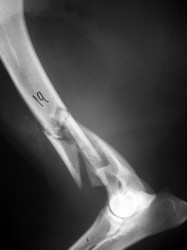

PRÁCTICAS CURSO DE FIJACIÓN EXTERNA PERFECCIONAMIENTO.

Húmero.